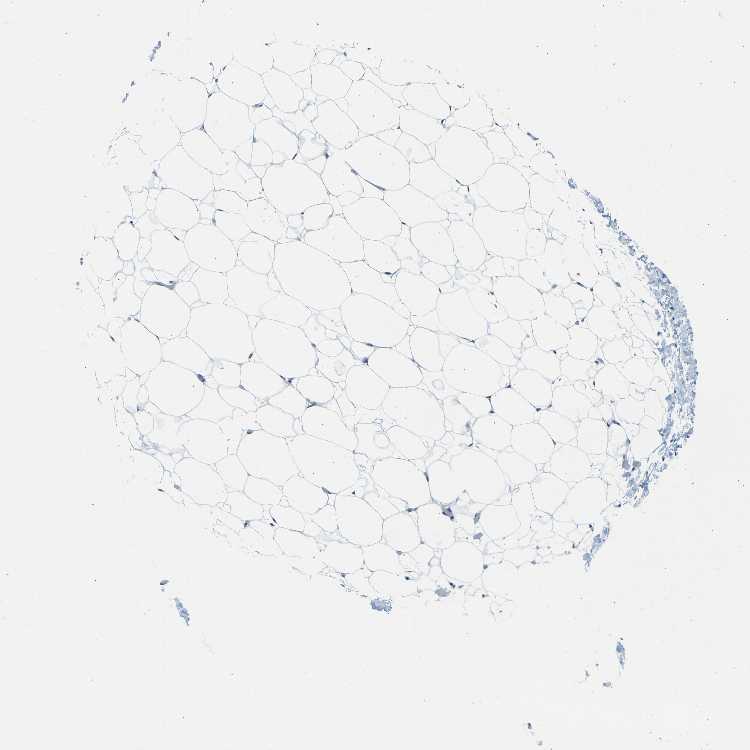

SOFT TISSUE 1 - Antibody stainingi

Antibody staining in the annotated cell types in the current human tissue is reported as not detected, low, medium, or high, based on conventional immunohistochemistry profiling in selected tissues. This score is based on the combination of the staining intensity and fraction of stained cells.

Each image is clickable and will lead to virtual microscopy that enables deeper exploration of all samples and also displays staining intensity scores, fraction scores and subcellular localization as well as patient and tissue information for each sample.

Antibody HPA012024

Chondrocytes Not detected

Fibroblasts Not detected